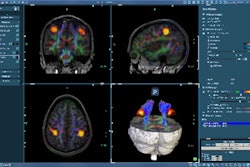

The MRI examinations were performed using a circularly polarized head coil in a conventional 1.5-tesla whole-body scanner (Magnetom Vision, Siemens Healthcare, Malvern, PA). DWI was performed using a single-shot echo-planar technique (TR/TE = 4,000/110 msec, 5 mm thick) in three spatial encoding directions and two b values (500, 1,000 sec/mm²).

Fifteen bilateral regions of interest were manually drawn on ADC maps generated when the images were reviewed. The brain regions were grouped for analysis into categories classified as peripheral gray matter, peripheral white matter, deep white matter, deep gray matter, and posterior fossa. Comparisons between the mean ADC values of the outcome groups and individual regions of interest were evaluated.